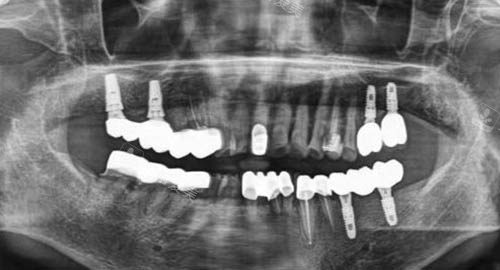

多颗牙齿种植ct

在种牙前,会为患者进行超全的口腔检查和详细的诊断,制定个性化的种植方案。

他们使用的种植体都是经过严格筛选的优质产品,具有良好的生物相容性和稳定性。

在种植过程中,医师们操作比较准、熟练,能够将种植体更准地植入到牙槽骨内,大大提高了种植的可行性。